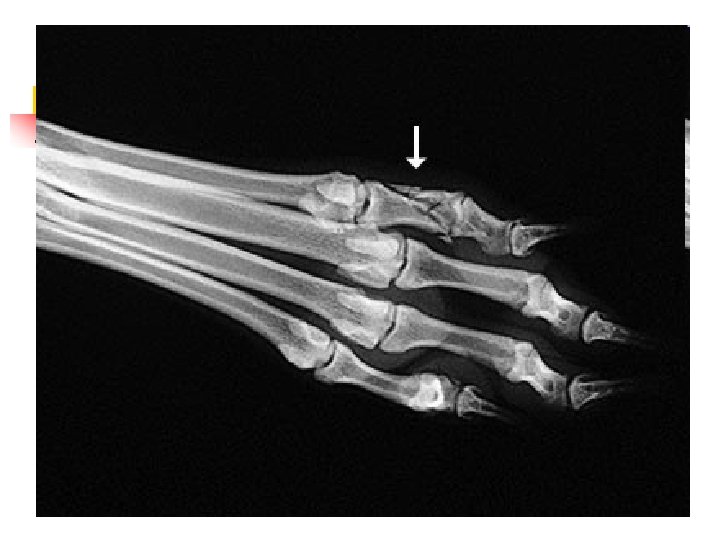

When Animals Limp n n n The good new is that 9 out of 10 limping animals have what we call soft tissue injuries a sprain, a pull, a bruise and only require exercise restriction to heal. However, 1 out of 10 animals with lameness has something more serious, and we can tell which ones by close observation of the patient walking and careful physical examination. In those cases, radiographs are used to make a diagnosis.

When Lameness isn’t Simple n n Sometimes when an animal limps the cause turns out to be something more serious than a simple injury. The doctors palpated a firm, painful lump in the leg this dog was favoring. Radiographs showed that the bone was expanded in that area, with a motheaten, hollowed-out center. These are classic signs of a tumor in the bone, known as an osteosarcoma.